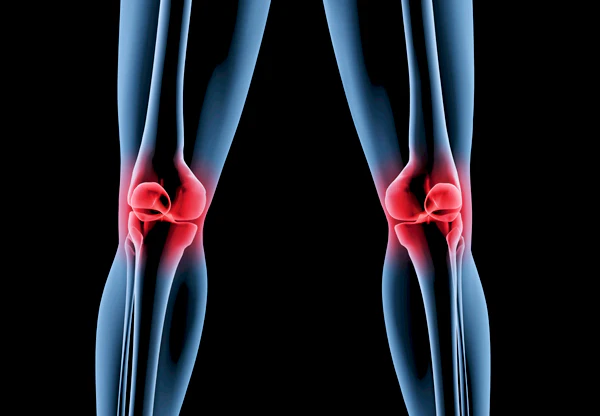

통풍을 적절히 치료하지 않을 경우, 발작성 관절염의 빈도가 증가하고 침범하는 관절 수도 더 많아지며, 회복에 필요한 시간도 증가합니다. 반복적인 관절염은 관절을 점차 손상시키며, 만성적인 관절염으로 진행될 수 있습니다. 또한 통풍성 결절이라 불리는 덩어리가 관절 주위나 피부 조직에 나타날 수 있습니다. 이러한 결절은 요산 결정체의 덩어리로 어느 부분에서든 형성될 수 있으며, 주로 팔꿈치, 귀, 손가락, 발가락, 발목 등에서 발생할 수 있습니다. 때로는 요로 결석을 형성하기도 합니다.

1) 한 군데 관절(엄지발가락, 발목, 무릎 등)이 갑자기 붓고 빨갛게 변하며, 손을 움켜쥘 수 없을 정도로 심한 통증이 발생합니다.

4) 엄지발가락 관절에 염증이 잘 발생하는 것이 특징이며, 무릎, 발, 발목, 손목, 팔꿈치 등 다른 관절에서도 발생할 수 있습니다.